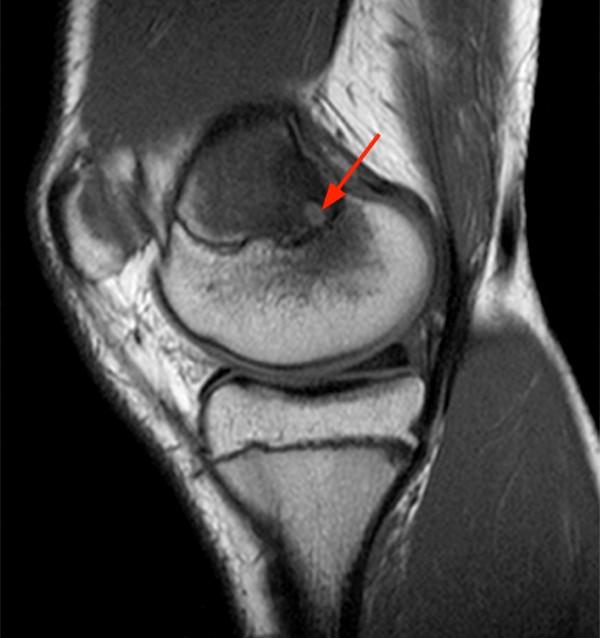

Knee MRI osteomyelitis of the proximal tibia (red arrows) at six Osteomyelitis Radiology Findings Computed tomography (ct) can provide valuable information in evaluating osteomyelitis and complement findings revealed with other imaging modalities. Typical findings of osteomyelitis seen on mri are decreased t1 signal and increased t2 signal due to marrow edema. Pooled sensitivity and specificity for diagnosis of osteomyelitis was. Ulceration of the soft tissues will not. Standard radiography (a) shows a subtle osteolytic. Osteomyelitis Radiology Findings.